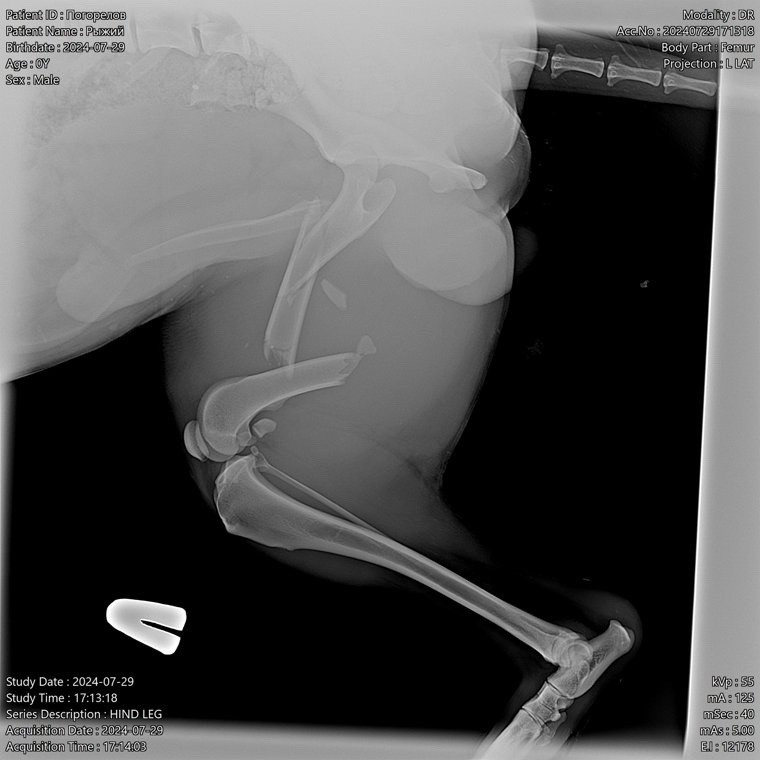

«Он жил в садах и был, как это часто бывает, ничейным, но при этом общим псом. Играл с детьми, гонял пришлых собак. Его любили и подкармливали, но вот его сбила машина, как итог – сложный оскольчатый перелом левого бедра. Травма действительно сложная, в нашем городе врачи не возьмутся его лечить, надо ехать в Екатеринбург», – рассказывают в ветклинике.

Сумма сбора внушительная – минимум 100 тысяч рублей. Возможно, что и этого не хватит. Ведь предстоит сделать первичную операцию, установить аппарат фиксации или пластины, затем последуют несколько месяцев восстановления в стационаре и повторная операция по снятию аппарата.